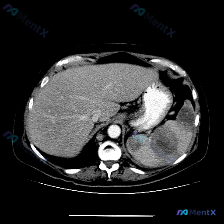

整理了一份肝脾同时出现多发占位的影像及鉴别思路,分享给大家。 --- 先看影像核心发现 这是一张增强腹部CT横断面(软组织窗): 1. 肝脏:肝左右叶弥漫分布多发、大小不一类圆形低密度灶,边缘相对清晰,部分病灶可见边缘强化/“靶征”; 2. 脾脏:脾脏实质内也有类似的低密度占位病变; 3. 其他:腹...